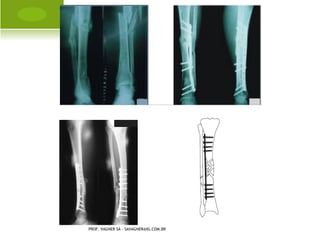

SUBTROCANTÉRICA

PROF. VAGNER SÁ - SAVAGNER@IG.COM.BR

DIÁFISE